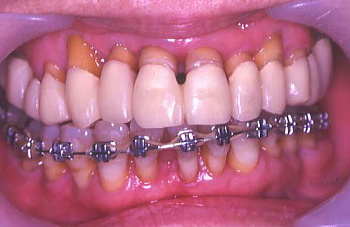

⑯ 下顎歯列の矯正中

⑰ 矯正治療後の状態